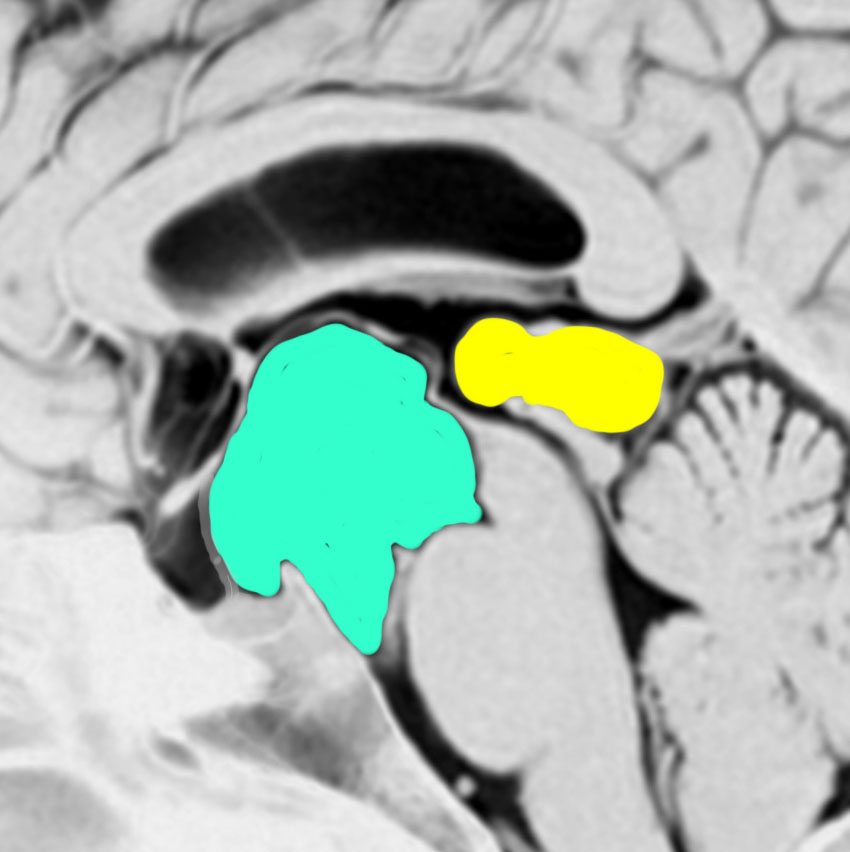

20代の女性に偶然見つかったものです。水色に塗ったのが鞍上部クモ膜のう胞 arachnoid cyst,黄色に塗ったのが松果体のう胞 pineal cystです。両方ともとても珍しもので,大きなのう胞です。クモ膜のう胞と松果体のう胞が同じ原因で形成されることを示唆しています。